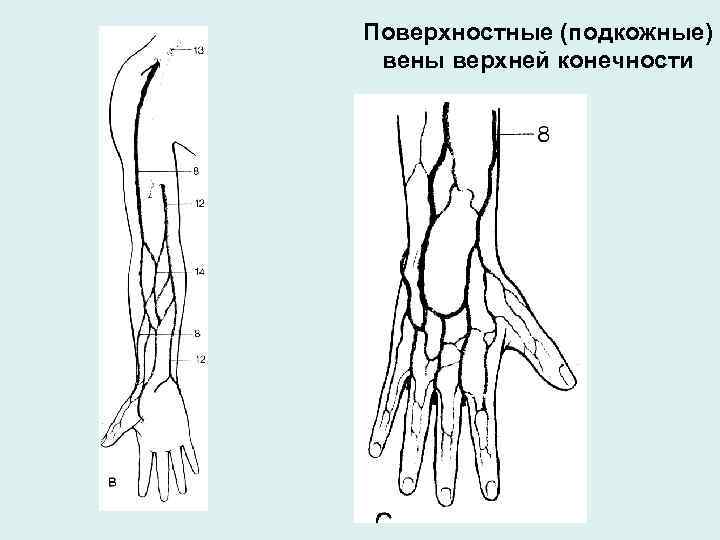

Поверхностные (подкожные) вены верхней конечности • Латеральная подкожная вена (v. cephalica) начинается на тыле кисти на лучевой стороне, впадает в подмышечную вену • Медиальная подкожная вена (v. basilica) начинается на тыле кисти на локтевой стороне, впадает в плечевую вену • Промежуточная вена предплечья начинается на ладони, впадает в промежуточную вену локтя • Промежуточная вена локтя - анастомоз

Поверхностные (подкожные) вены верхней конечности

Поверхностные вены верхней конечности Варианты строения